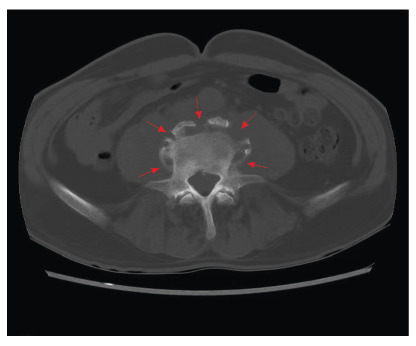

The appearances of a parrot's peak and petal rims in brucellar spondylitis.